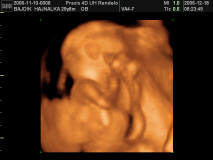

Melcsinek ez az arányszám valóban jó. Ehhez nézik ám az életkort is, és az minél magasabb, annál rosszabb arányszám jön ki. A határérték azt hiszem 1:150, és ez konkrétan azt jelenti, hogy a baba 1%(!) valószínűséggel Down kóros. Ha ettől rosszabb az arányszám, csak akkor javasolják az amniot. Ennek a markernek a megbízhatósága 95%, az amnióé 97 v. 98%! Tehát az se 100%!

Szerintem ne ess pánikba, a 2,9mm nem jelent egyértelműen bajt! Tényleg! Szerintem neked az a 18. heti vizsgálat egy genetikai uh lesz. Én is megyek ilyenre hétfőn. Nekem azt mondták, hogy ez az uh azért olyan fontos (egyébként úgy tudom kötelező is ), mert itt nagyon alaposan meg tudják nézni a babát: a szívkamráitól kezdve az agyáig mindent!